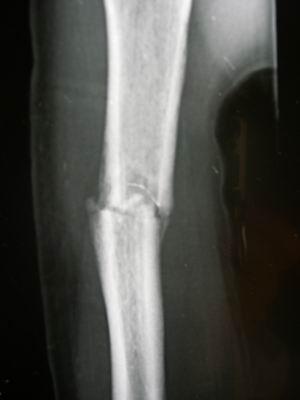

骨痂片子,长了骨痂的x光片图

是外踝骨折有碎片,但是不知道自己是哪里看不懂,想看下骨折线骨痂在哪

45天拍的片子,肉骨长了骨痂,胫骨没长,还用石膏固定吗?

术后三个月,x光片可见骨痂形成,患者恢复良好!家属满意!继续观察!

09-2-20治疗后55天.骨痂形成良好,局部无压痛和纵扣痛,去骨牵引.

胫腓骨骨折